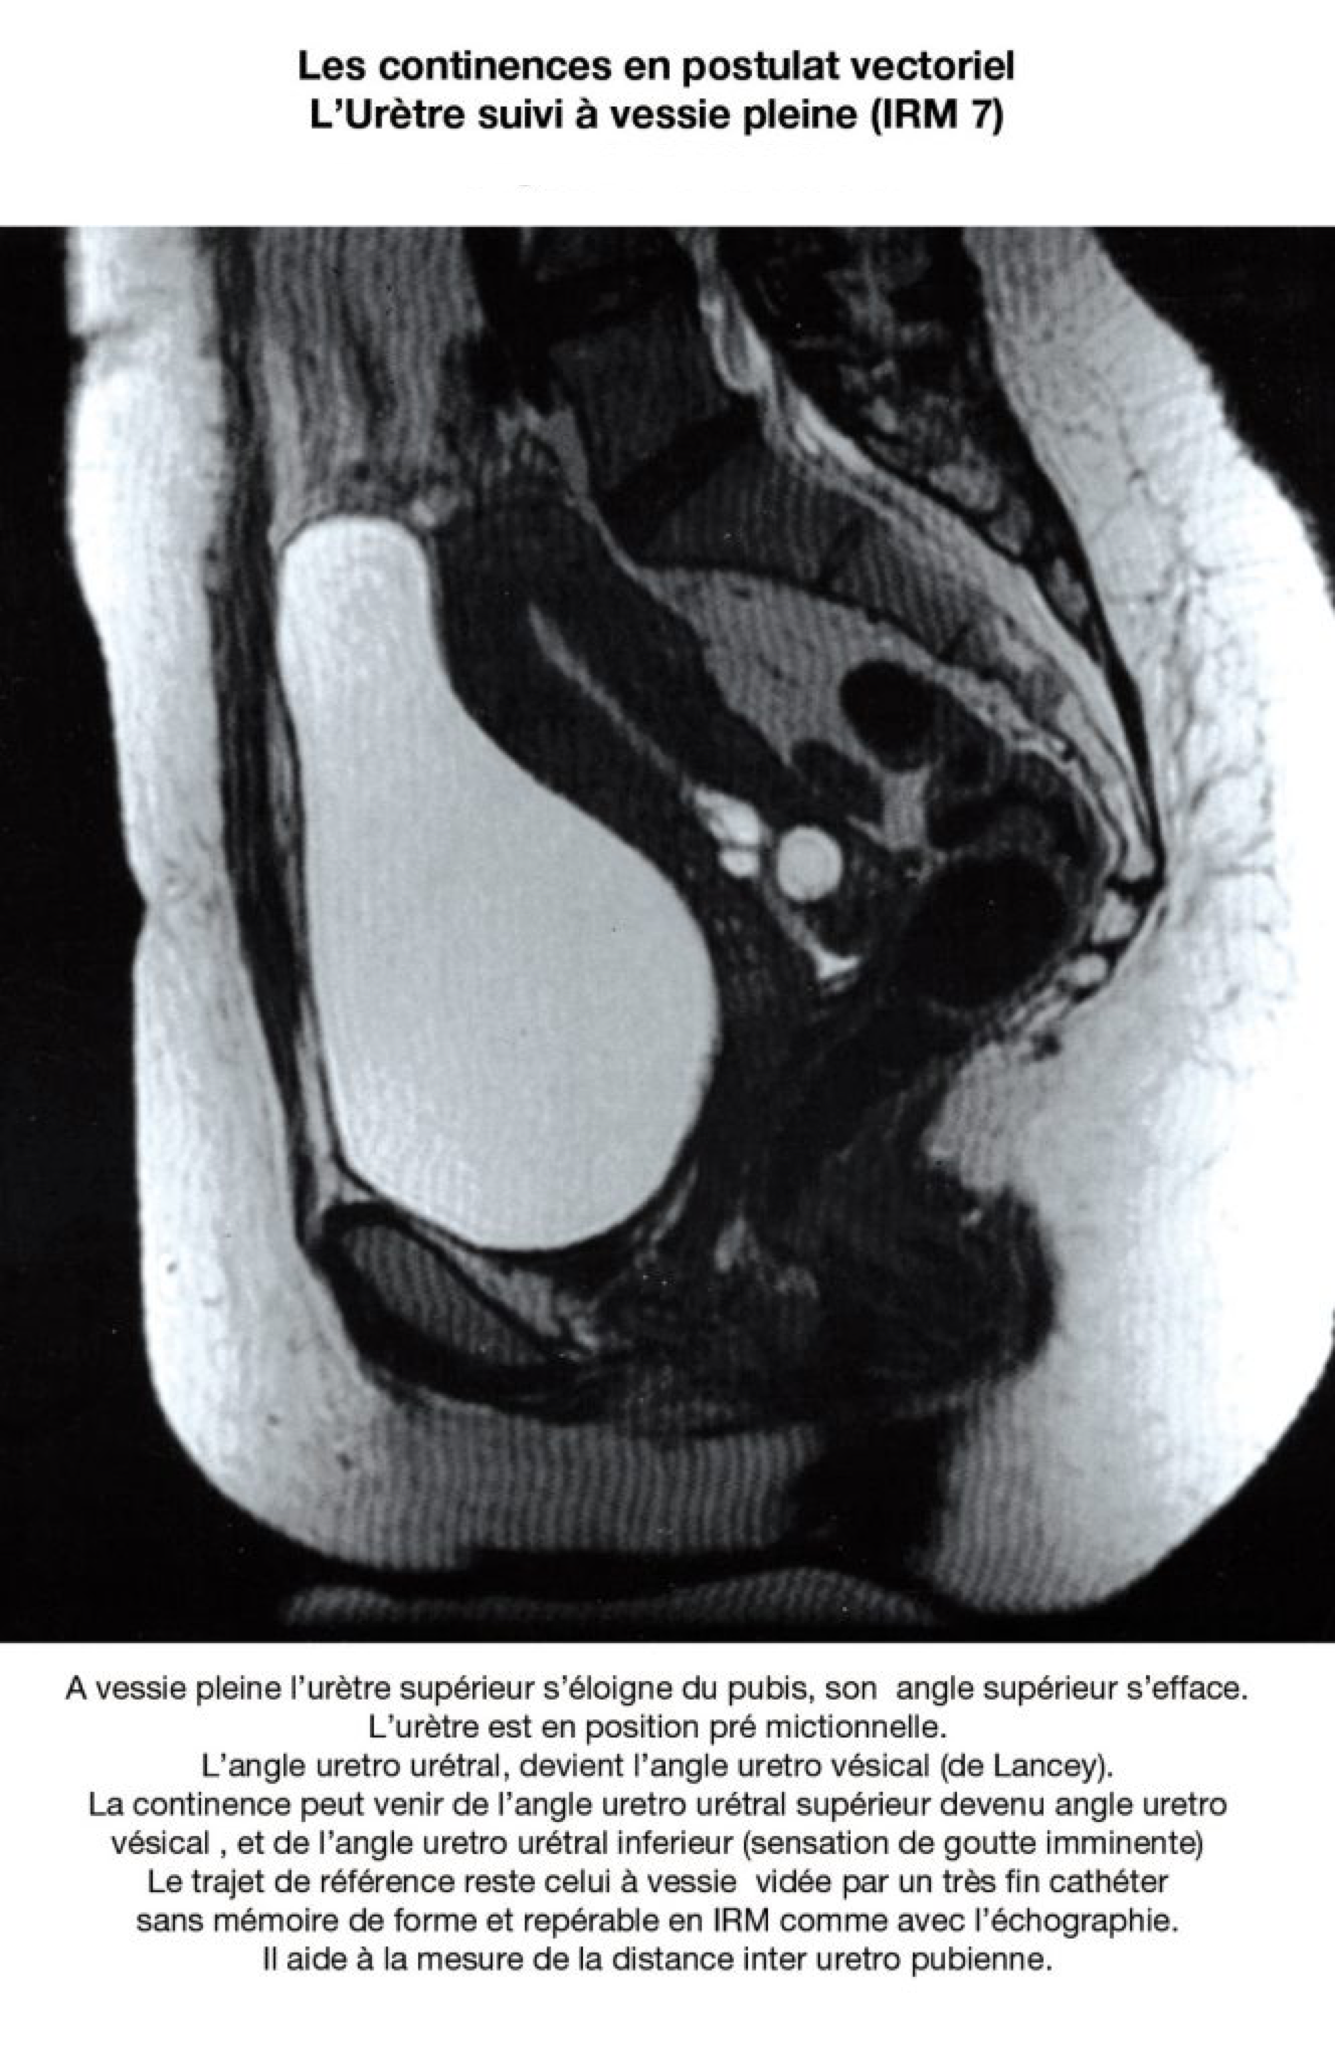

En postulat vectoriel, leur rôle essentiel pourrait être (???) celui de propriocepteurs ; et ils accentueraient et participeraient aux effets de clôture lors des glissements du tissu visco élastique pelvien. Divers arguments plaident en faveur de ces hypothèses : Pour l’urètre : 25% des vessies sont continentes à sphincter ouvert (ref 5). L’urètre continent de l’IRM n’est pas rectiligne. Il décrit un trajet en zigzag et la distance uretro pubienne faible. (Sa plicature peut être un mécanisme de continence). L’urètre continent n’est rectiligne que lors de l’incontinence physiologique, la miction (uretrographie mictionnelle).

La continence des urines, l’efficacité de la manœuvre de Bonney et celle des bandelettes sous urétrales trouvent une logique commune : la reconstitution du zigzag urétral, et le raccourcissement de la distance pubo urétrale. L‘échographie, ou l‘IRM devraient permettre la mesure de la distance uretro retro pubienne à vessie vide, et lui donner un sens diagnostique et peut être pronostique. L’effet supposé de clôture, du zigzag urétral permet aussi de comprendre la rapidité de la récupération urinaire post partum, facilitée par la rétraction physiologique rapide et spontanée des ligaments pubo urétraux.

Elle intervient sans que la longueur du hiatus uro génital n’ait eu le temps de rétrécir de façon significative. Et on observe que la continence urinaire se récupère, même si les vecteurs de pression abdominale restent un tant soit peu orientés vers le prolapsus. La rétraction post hormonale gravidique du tissus visco élastique est plus rapide, plus spontanée et plus efficace que la récupération musculaire ; s’agissant de récupérer le volume ou la trophicité musculaire. Le suivi des effets de la rééducation et de la physiothérapie pourrait être suivi et validé par l’échographie, même si le repérage de l’angle uretro urétral et de la distance uretro pubienne ne peuvent se faire que à vessie vide, et par voie transperineale.